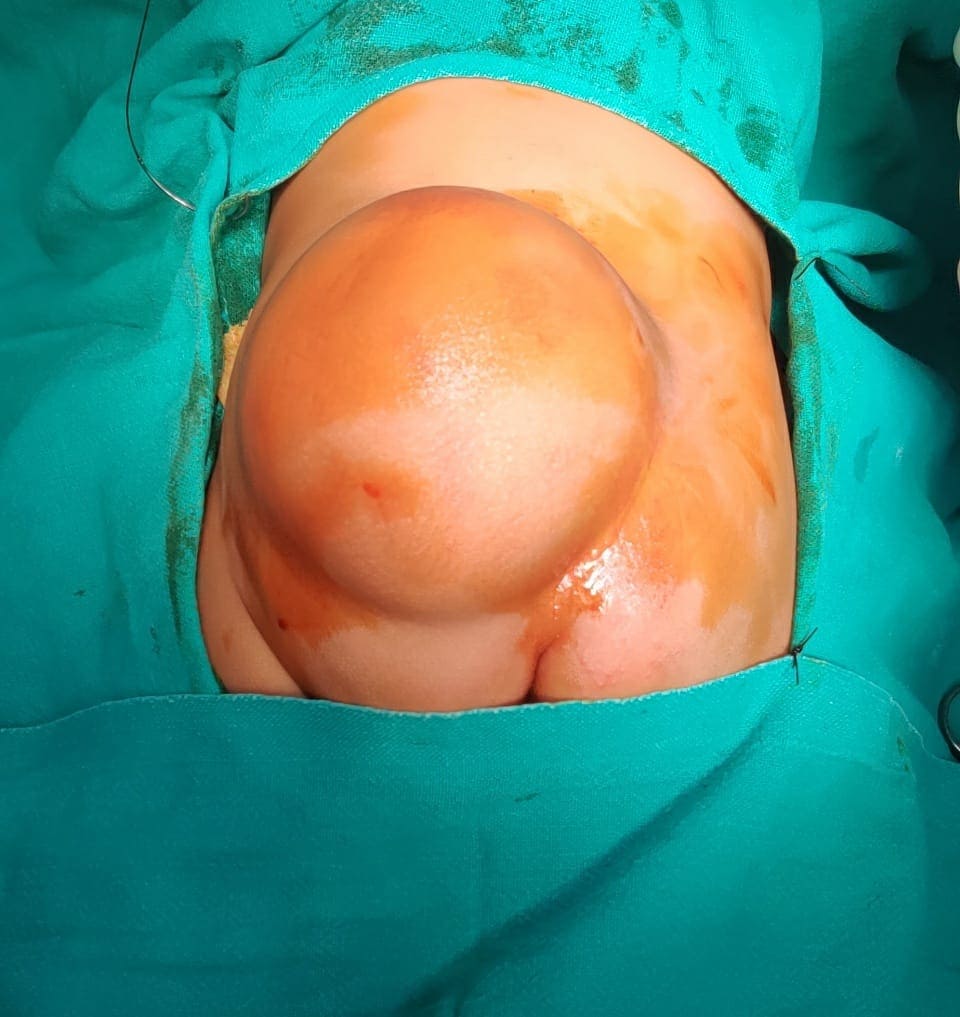

Anorectal malformation with scrotal fistula with bifid scrotum

Creat neoanus with improvement of scrotal appearance as normal